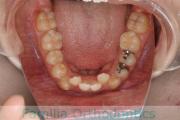

No.22V-785

- 叢生

- 33歳

- 女性

- 抜歯部位

- 上:

- 83|4

- 下:

- 8448

- 主な使用装置:

- FEA 022

- 治療にかかった費用:

- 92万円

咬み合せが悪く、ガタつきを治したいということで来院されました。右上犬歯の著しい位置異常があるため、様々な抜歯部位・治療方針の候補がありましたが、最終的には右上は犬歯、残りは小臼歯抜歯をしてマルチブラケット法にて治療を行いました。丸2年、25回程度の通院が必要でした。

右上犬歯の移動を無理に行うと、強い歯肉退縮を起こすリスクが高かったと考えています。